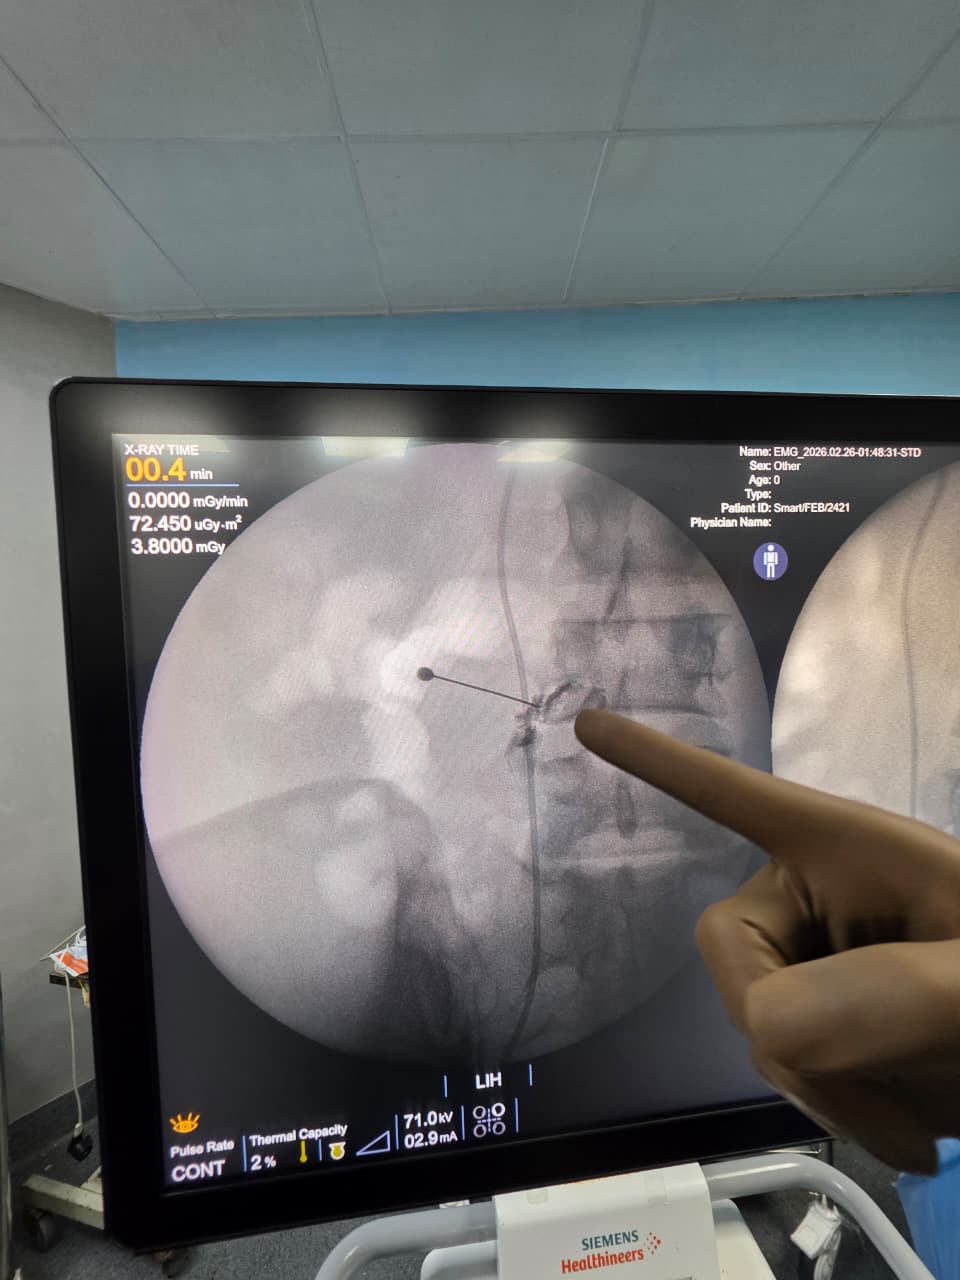

Procedures